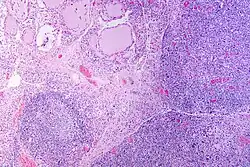

| A micrograph of the thyroid of someone with Hashimoto's thyroiditis | |

Microscopic examination (histology) will show lymphocytes (including plasma B-cells) diffusely infiltrating the parenchyma.[55] The lymphocytes are predominately T-lymphocytes with a representation of both CD4+ and CD8+ cells.[5] The plasma cells are polyclonal, with present germinal centers resembling the structure of a lymph node[5] (also called secondary lymphoid follicles, not to be confused with the normally present colloid-filled follicles that constitute the thyroid).[55]

In late stages of the disease, the thyroid may be atrophic.[10] Colloid-filled follicles shrink, and the cuboidal cells that usually line the follicles become Hürthle cells.[5] Fibrous tissue may be found throughout the affected thyroid as well.[5] Severe thyroid atrophy presents often with denser fibrotic bands of collagen that remain within the confines of the thyroid capsule.[55]

Generally, pathological findings of the thyroid are related to the amount of remaining thyroid function — the more infiltration and fibrosis, the less likely a patient will have normal thyroid function.[5] A rare but serious complication is thyroid lymphoma, generally the B-cell type, non-Hodgkin lymphoma.[24]